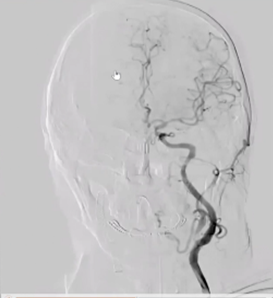

术前右侧椎动脉造影

病历夹什么径技·第152期|串联营病历夹:川陕大营_https://www.jmylbn.com_新闻资讯_第11张

病历夹什么径技·第152期|串联营病历夹:川陕大营_https://www.jmylbn.com_新闻资讯_第12张

病历夹什么径技·第152期|串联营病历夹:川陕大营_https://www.jmylbn.com_新闻资讯_第13张<<滑动查看下一张图片>>

术前左侧椎动脉造影

病历夹什么径技·第152期|串联营病历夹:川陕大营_https://www.jmylbn.com_新闻资讯_第14张

病历夹什么径技·第152期|串联营病历夹:川陕大营_https://www.jmylbn.com_新闻资讯_第15张

病历夹什么径技·第152期|串联营病历夹:川陕大营_https://www.jmylbn.com_新闻资讯_第16张

<<滑动查看下一张图片>>

左侧颈总动脉造影

病历夹什么径技·第152期|串联营病历夹:川陕大营_https://www.jmylbn.com_新闻资讯_第17张

右侧颈总动脉造影

病历夹什么径技·第152期|串联营病历夹:川陕大营_https://www.jmylbn.com_新闻资讯_第18张

病历夹什么径技·第152期|串联营病历夹:川陕大营_https://www.jmylbn.com_新闻资讯_第19张

病历夹什么径技·第152期|串联营病历夹:川陕大营_https://www.jmylbn.com_新闻资讯_第20张